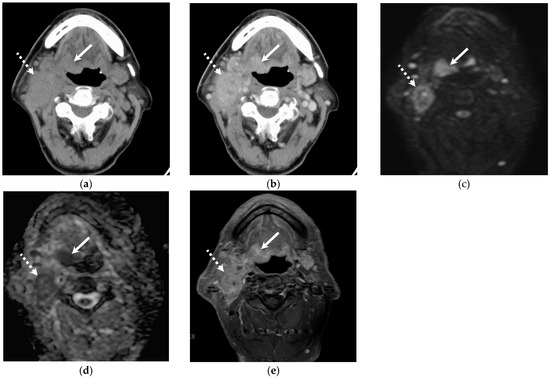

3.2. Quantitative and Qualitative Imaging Findings of the Primary Lesion

3.3. Quantitative Imaging Findings of Cervical Lymph Node Metastasis

3.4. Qualitative Imaging Findings of Cervical Lymph Node Metastasis

4. Discussion